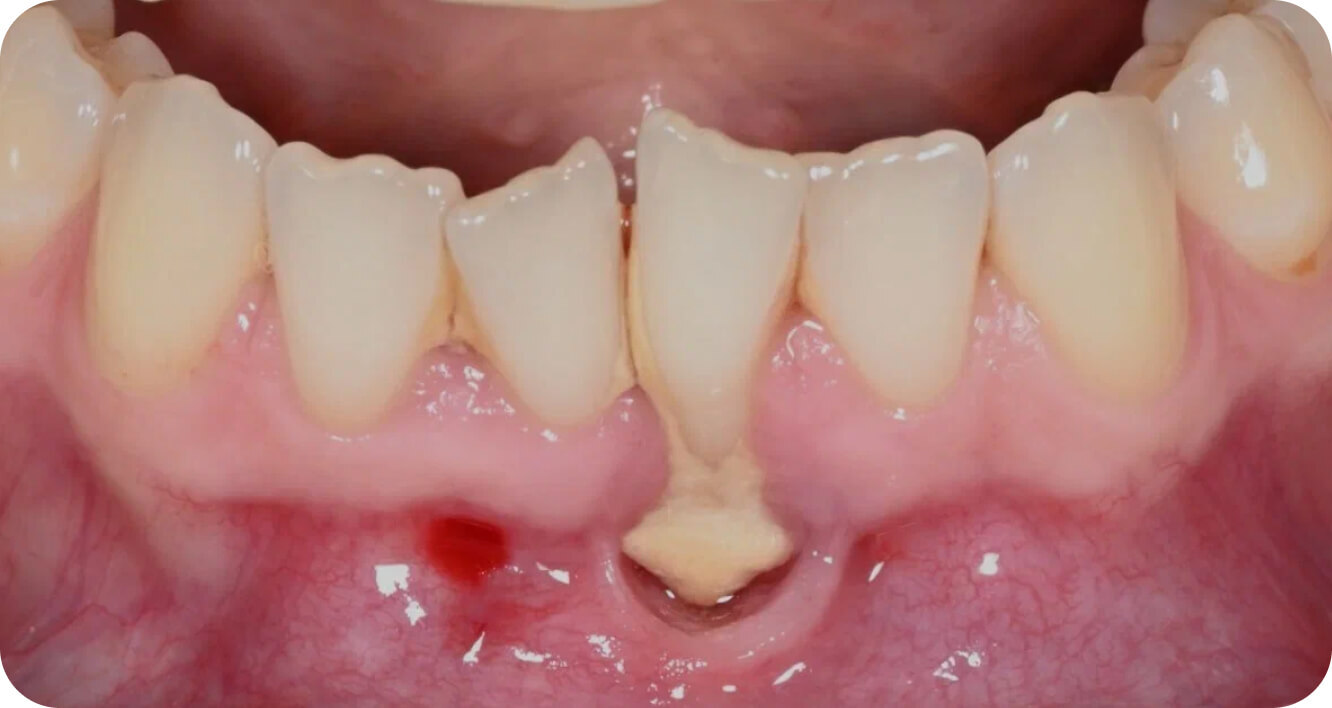

Мои работы

до/после

Интересные

случаи